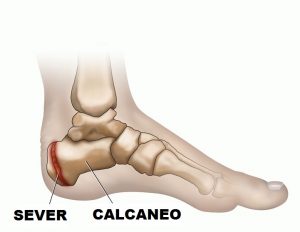

L’os trigonum è un ossiculo accessorio presenta a ridosso del comparto posteriore della caviglia, con variabili dimensioni.

Va distinto dallo pseudo os trigonum creato da un distacco del margine osteofitario posteriore dell’astragalo e quando crea un documentato conflitto posteriore nella caviglia può essere asportato in artroscopia

c) La sindrome da impingement posteriore, tipica dei danzatori e dei ginnasti, è di solito determinata dalla presenza di un os trigonum o da un tubercolo posteriore dell’astragalo prominente che determinano una reazione infiammatoria sinoviale a tale livello. Ci sono, comunque, altre cause ossee e dei tessuti molli, che giustificano il termine generico di impingement posteriore di caviglia. All’esame obiettivo si hanno dolore durante la flessione plantare passiva e dolorabilità alla palpazione della porzione posteriore della caviglia con possibile limitazione alla flessione plantare. Queste alterazioni sinoviali sono ben dimostrabili all’esame RM che mostra la distensione di queste strutture sinoviali, dovuta alla presenza di versamento, documentato da una tipica iperintensità di segnale nelle sequenze T2 pesate e ipointensità nelle sequenze T1 pesate; anche le cause di impingement sono dimostrate con questa tecnica .

Se osserviamo con attenzione il margine posteriore del corpo dell’astragalo, vediamo che questo presenta una sporgenza, detta tubercolo posteriore che, nella maggior parte delle persone, si unisce al resto del’osso tra i nove ed i dodici anni di età (Kadel et al., 2000): in una certa percentuale di persone, tuttavia, questo tubercolo resta separato dal resto dell’osso e prende il nome di os trigonum, a causa della sua forma vagamente triangolare; in altri soggetti, invece, quando il tubercolo posteriore dell’astragalo è particolarmente grande ed “ingombrante”, viene definito come processo di Stieda (Clippinger, 2007).

In presenza delle due condizioni sopra descritte, quando il danzatore forza il movimento di massima flessione plantare, la porzione posteriore della capsula articolare della caviglia ed i tessuti molli adiacenti possono essere bruscamente compressi contro il margine posteriore della tibia dando origine, appunto, ad una limitazione della mobilità articolare. Tale situazione si verifica soprattutto se, per stendere la punta, viene utilizzata prevalentemente la contrazione del muscolo tricipite surale: la brusca sollecitazione del tendine d’Achille, infatti, richiama troppo velocemente indietro il calcagno e l’astragalo si blocca all’interno della pinza mentre la presenza dell’os trigonum o del processo di Stieda comprime ulteriormente capsula e tendini posteriori.